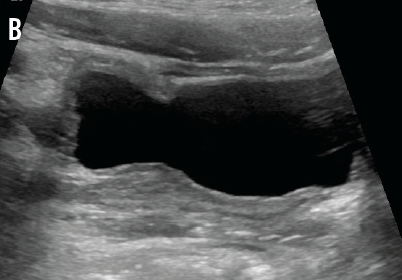

IgA and C4 values were normal, and the C3 value was slightly elevated, which decreased the likelihood of IgA nephropathy, PSGN, and lupus nephritis. Normal kidney function made ATN less likely. A normal IgA level and a lack of skin or joint manifestations ruled out HSP. Urine and stool bacterial cultures returned negative. Renal ultrasonography demonstrated normal kidneys with minimal bladder wall thickening (A and B) and an incidental finding of uterus didelphys. The patient continued to pass clots in her urine, prompting further investigation for viral hemorrhagic cystitis. Urine polymerase chain reaction (PCR) test results were negative for BK virus, but PCR results for urine and serum adenovirus returned positive on hospital day 3.